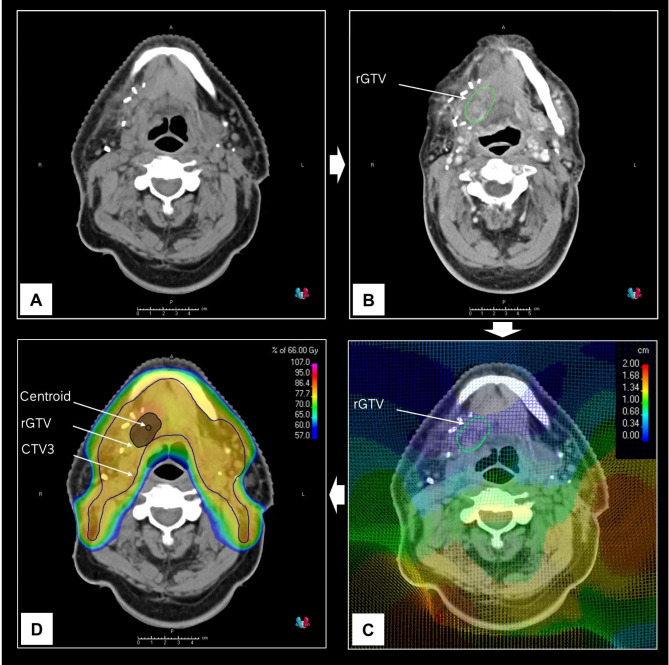

Materials and methods: We retrospectively reviewed 203 HNSCC patients (75% HPV-negative, 25% HPV-positive) treated with curative intent postoperative (chemo)radiotherapy from 2017 to 2021. Recurrence imaging was co-registered with planning CT, and recurrent tumor volumes were dosimetrically compared to the target volume dose and spatially analyzed using a center-of-mass-based approach. We classified five recurrence types: A (central high-dose), B (peripheral high-dose), C (central intermediate- or low-dose), D (peripheral intermediate- or low-dose), and E (extraneous dose).